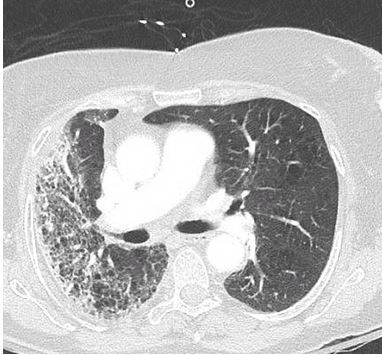

Her past medical history was significant for squamous cell skin cancer of the right shoulder which was treated with surgical excision (Figure 1) followed by 7 weeks of radiation therapy. Results of a CT scan of the chest are seen in Figure 2.